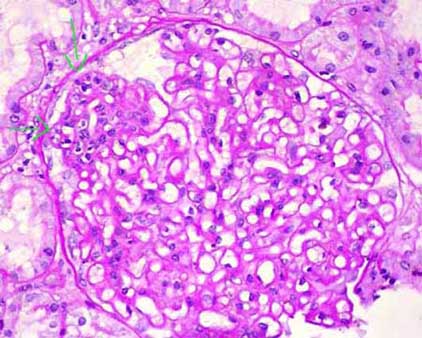

Figure 5. With PAS stain the thickening of capillary walls is evidenced; there is no a noticeable mesangial widening. In this case there is also a segment with endocapillary proliferation (arrows); this finding must suggest the possibility of a secondary MGN. (PAS, X.400).

In STAGE II the histologic

findings with light microscopy allow an easier diagnosis. The glomerular architecture

is preserved and the capillary walls appear thickened with routine stains (Figure

1). The cellularity usually is not increased (if present it suggests a secondary

MGN) and the capillary lumina are ample. There is formation of material with

similar aspect to the GBM (although with different composition) that projects

perpendicularly to this one: “spikes” (Figure 2). These spikes are

originated in reaction to the deposits and go progressively surrounding them.

This material is composed of type IV collagen and noncollagenous components:

laminin, proteoglycans and vitronectin, and could be originated by mediators

produced by the podocyte or another mechanism that stimulates changes in the

GBM. In some sections are well observed the spaces or holes that produce the

immune deposits in the outer aspect of the GBM, with the center of the hole

corresponding to the immune deposit and the periphery to the GBM-like material.

In some cases these holes have an irregular form that gives a reticulated aspect

to the GBM (Figure 4). In some cases we find segmental cellular proliferation

(Figure 5), but in these cases we must consider the possibility of a secondary

MGN; in other cases there will also be segmental and focal sclerosing lesions

(Figure 6).